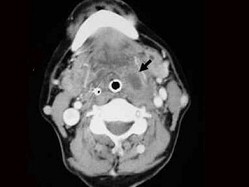

3.女,57岁,颈部不适,CT如图所示,应诊断为 ( )![]() ![]() ![]() ![]() |

| 正确答案:C |